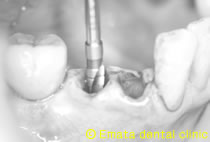

2ヶ月後に手術野をとりインプラントを入れた状態です。

外側骨がないのがわかりますね。

インプラントが骨内にはいっているので難しいケースではありません。